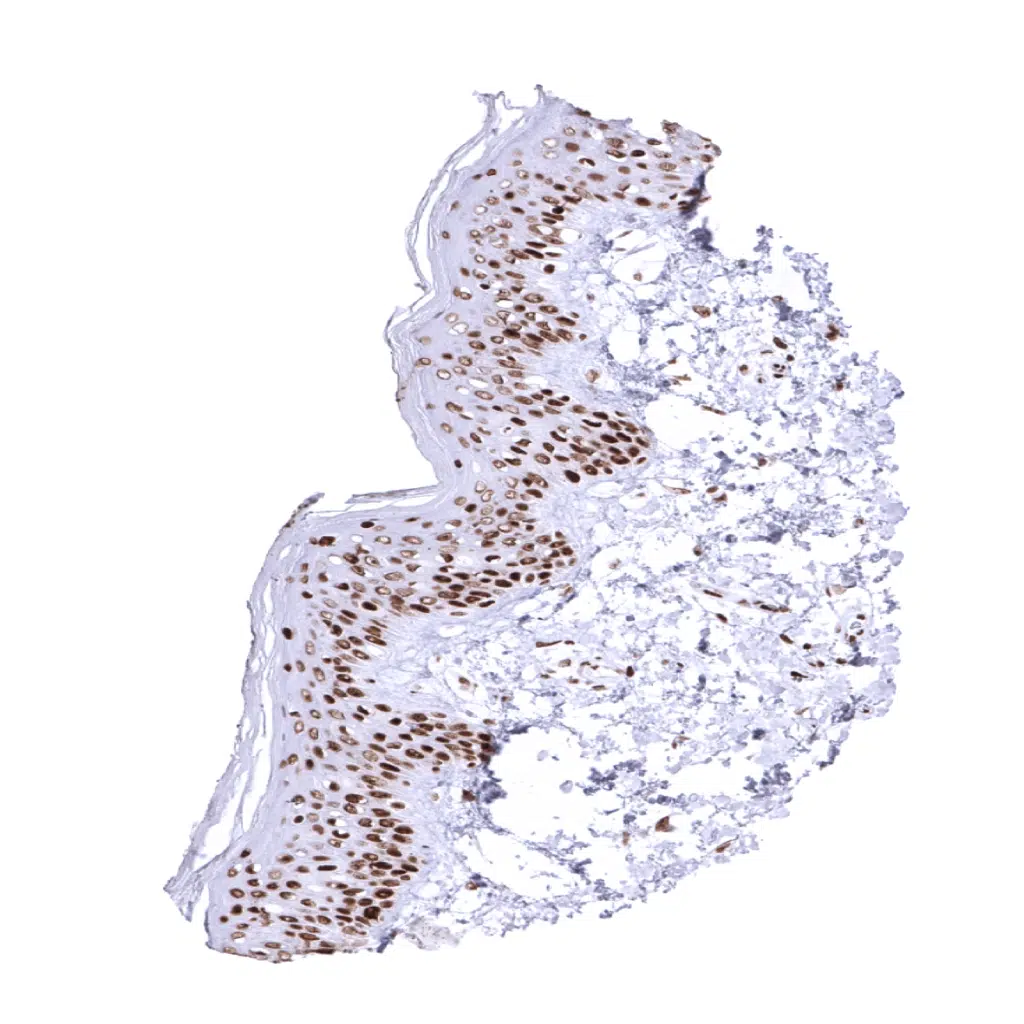

MSH2 antibody [MSVA-902M] HistoMAX

Skin